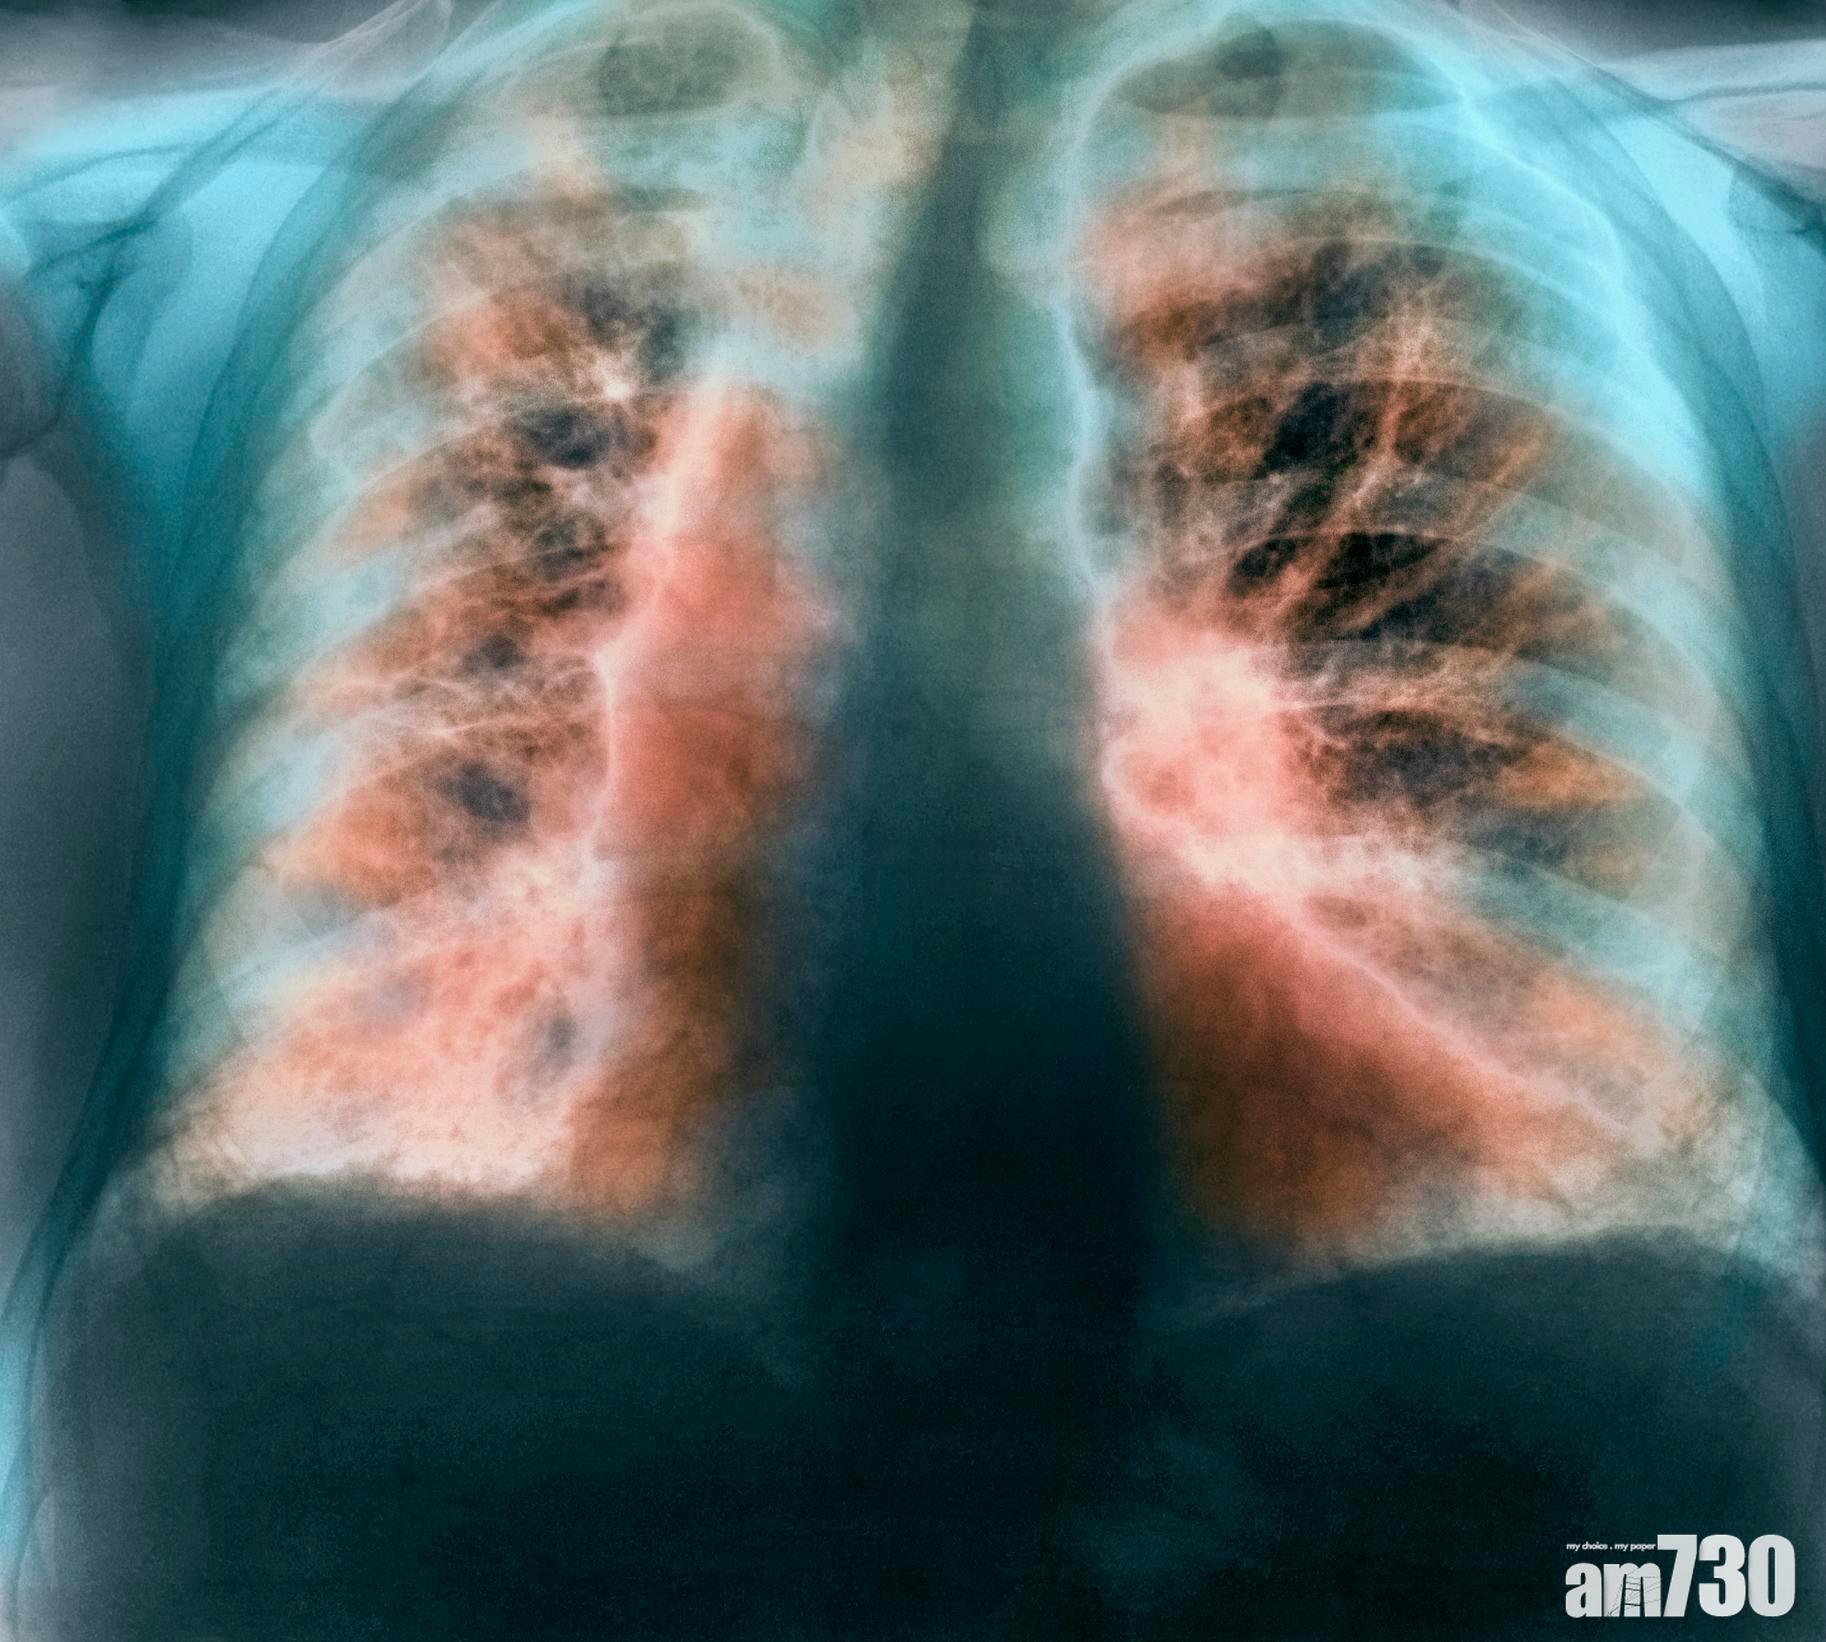

這種病因不明,但持續地肺間質因廣泛纖維化而造成的肺組織增厚,最終令肺部喪失正常氧氣交換功能。(互聯網圖片)

這種病因不明,但持續地肺間質因廣泛纖維化而造成的肺組織增厚,最終令肺部喪失正常氧氣交換功能的致命疾病「特發性肺纖維化」,估計在英國每年造成約5,000人死亡,與患白血病死亡人數相若。負責今次研究,曼徹斯特大學感染、免疫和呼吸道內科專家John Blaikley博士表明,從小鼠模型發現通過改變生理時鐘機制,有可能破壞因過度修復而造成疾病的纖維化過程,為治療或預防開闢了新途徑。

「我們體內的時鐘幾乎調節著人體每個細胞,24小時循環不息地進行如睡眠、荷爾蒙分泌和新陳代謝等許多過程。」而在肺部,時鐘主要位於空氣輸送通道的氣道中。但是研究小組發現,在肺纖維化病的患者中,這些時鐘波動會延伸到稱為「肺泡」Alveoli的肺部支氣管末端小氣囊。研究人員利用英國生物銀行的人類數據表明,引致肺纖維化與睡眠時間長短有所關係。跟每天睡眠7小時的人相比,報告發現每天規律睡眠4小時或更少的人,其患肺纖維化的機會增加了一倍,至於每天睡眠11小時或更長的人,患病的機會更增加了三倍。從中團隊發現一種重要時鐘蛋白Clock Protein「REVERBα」能夠改變肺纖維化中一種重要蛋白的產生,減少患者肺片中造成問題的膠原蛋白,為醫療帶來曙光。John Blaikley博士補充,「仍然需要進一步研究來加強肺纖維化和睡眠兩者的關係,如果結果得到證實,那麼最佳時間睡眠可能會減輕這種破壞性疾病的影響。」